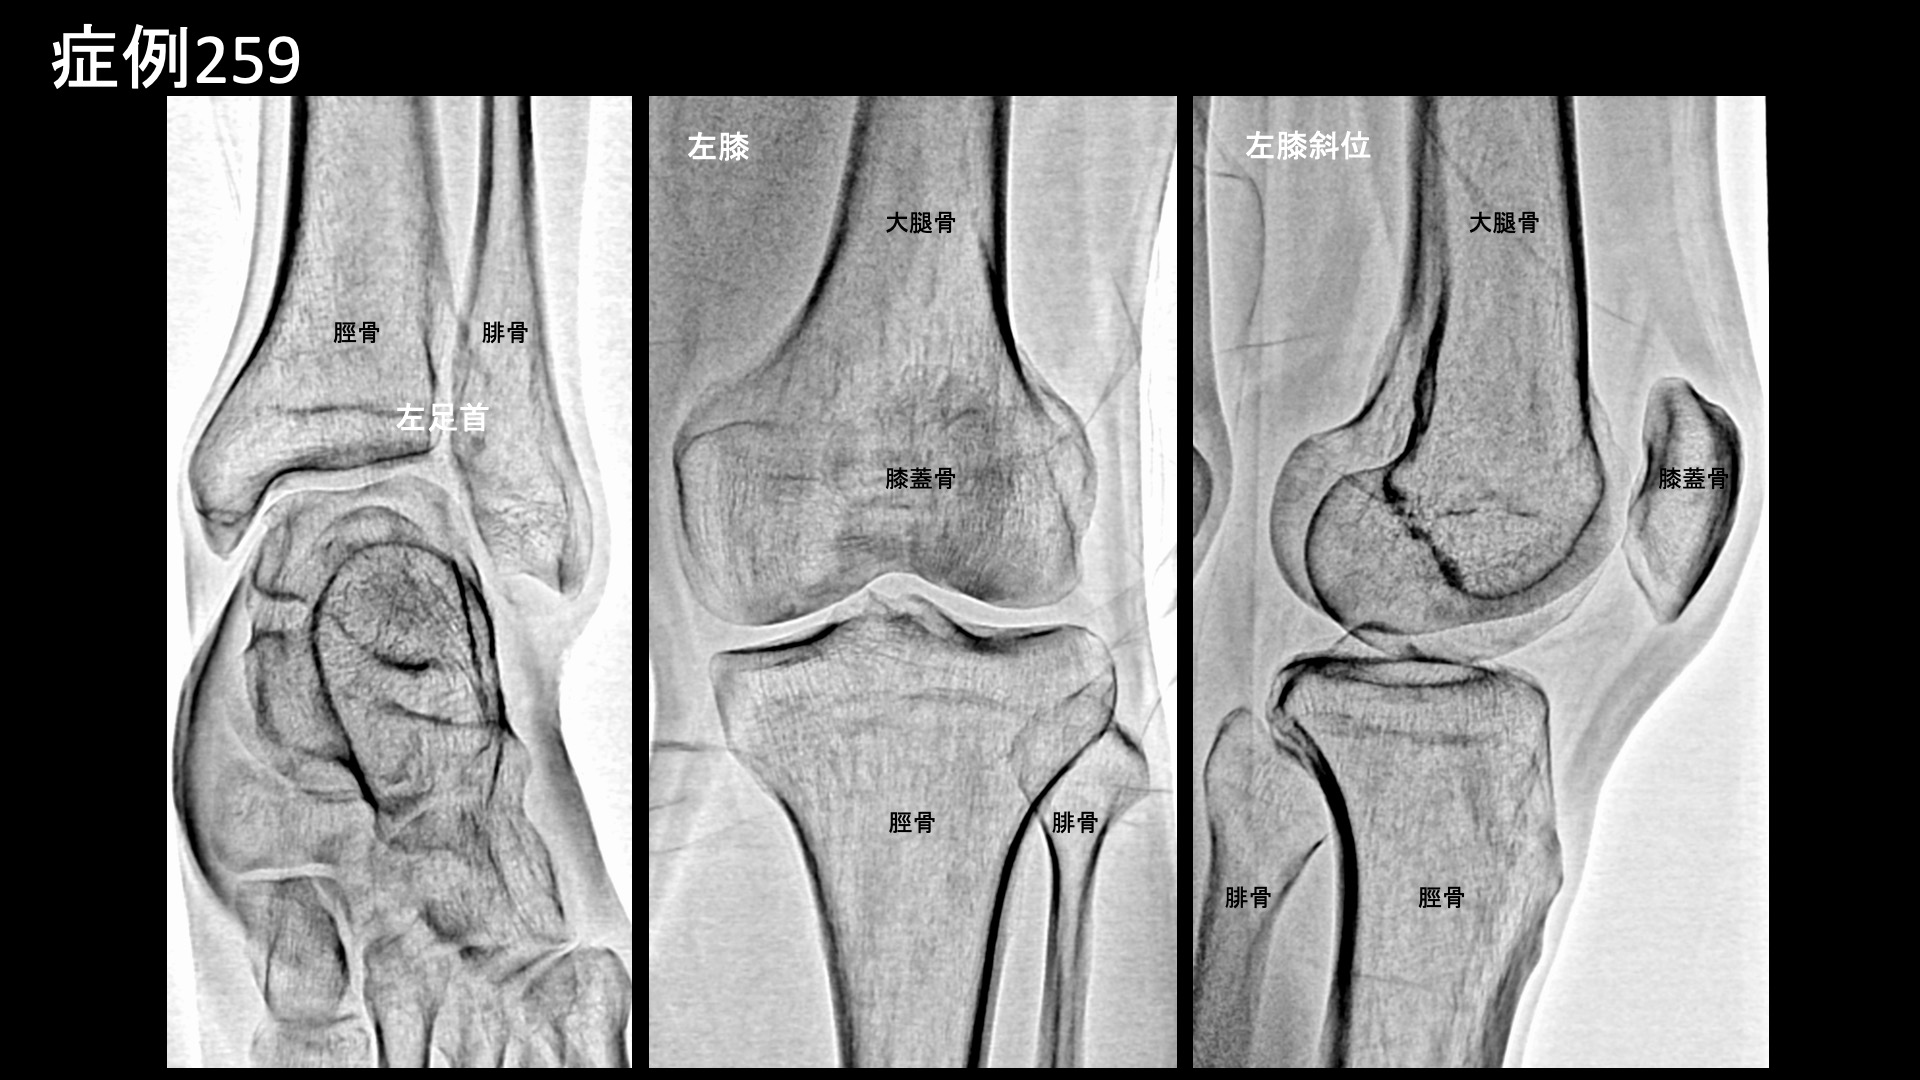

膝:変形性膝関節症など 【50代:男性】3年間治らなかった、走り始めから生じる膝の内側下方(鵞足部)の痛みに対するモヤモヤ血管治療(鵞足炎、膝蓋下脂肪体炎、反復性足関節捻挫) 2026.02.03 鴨井院長による動画解説 受診までの経過 3年前から左膝の痛みがありました。日常生活ではそれほど気にならないものの、走ると、走り始めから痛みがありました。少し曲げるくらいが最も痛み、自分では鵞足炎かなと思っていました。また、左足首は以前から捻挫を繰り返していました。以前受けた腰のカテーテル治療が良く効いたことから、改めて当院にご相談されました。 診察時の所見 疼痛部位は鵞足部および膝のお皿の下方でしたが、圧痛は目立ちませんでした。エコー検査では明らかな器質的異常は認められませんでした。レントゲンでは、膝関節に異常はなく、足首(足関節)では軽度の骨棘形成が見られました。また、扁平足であり、アキレス腱付着部において踵骨棘も認められました。立位ではいわゆる外反扁平をきたしており、捻挫を繰り返してきたことに合致していました。以上より、左膝蓋下脂肪体炎および鵞足炎の疑い、反復性足関節捻挫と診断しました。治療適応と判断し、モヤモヤ血管(病的新生血管)に対する運動器カテーテル治療(微細動脈塞栓術)を受けていただきました。 治療の所見 血管造影を行うと、内側下膝動脈でモヤモヤ血管が濃染像として描出されました。鵞足炎に合致した所見です。外側下膝動脈でも同様にモヤモヤ血管を認めましたが、こちらは膝蓋下脂肪体炎を反映しているものと考えられました。足関節ではモヤモヤ血管は画像上それほど目立ちませんでしたが、それぞれ治療を行いました。いずれも治療後モヤモヤ血管は画像上速やかに消失しました。その他複数箇所の治療を行い終了しました。 治療後の経過 治療当日は腫れぼったい感じがしていましたが、翌日から痛みが消失しました。治療後2週間、小走りでも大丈夫でした。足首はぷらんぷらんと不安定だったのが、しっかりしてきて安定感が増した感じがしました。足首までこんなによくなるのは不思議、もっと早く受ければ良かったと言われました。非常に経過良好でしたので、治療後3ヶ月の再診で問題がなければ終診予定としましたが、その再診時には、小走りをしても痛みが生じることはなく、足首も安定しているとのことでした。その後も順調に経過されています。 日常生活で支障をきたすほどの痛みではなく、いわゆるスポーツ障害の範疇での鵞足炎、さらに反復性足関節捻挫を合併した症例でした。鵞足炎は早期から改善することが多い疾患の一つですが、まさにそうした経過でした。扁平足でかつ足首が外にたわんで見える場合、外反扁平と呼ばれますが、こうした構造になっていると足首がぐにゃっと外側に倒れこんで捻挫を起こしやすいです。実際には靭帯が傷むため、繰り返していると足関節の不安定感につながったり、モヤモヤ血管が居つくことにより一定の痛みや違和感が持続したりすることにもなります。こうした反復する捻挫は、実はモヤモヤ血管治療の良い適応であり、治療すると捻挫をきたしにくくなったり、本症例のように安定感が増したりします。あまり知られていない良い治療適応の一つですので、思い当たる方はご相談いただければと思います。 鵞足炎の詳細はこちら 【90代:女性】90歳代高齢患者を悩ませた腰椎固定術後の腰臀部痛、股関節痛、坐骨神経痛、首肩こりがモヤモヤ血管治療で驚くほど早期から改善した実例(腰椎固定術後、仙腸関節障害、筋・筋膜性疼痛症候群、脊柱管狭窄、首肩こり) 前の記事 【40代:男性】3回目の新型コロナウイルスワクチン接種後に3年間悩まされた石灰沈着性腱板炎による肩の痛み(石灰沈着性腱板炎、SIRVA) 次の記事